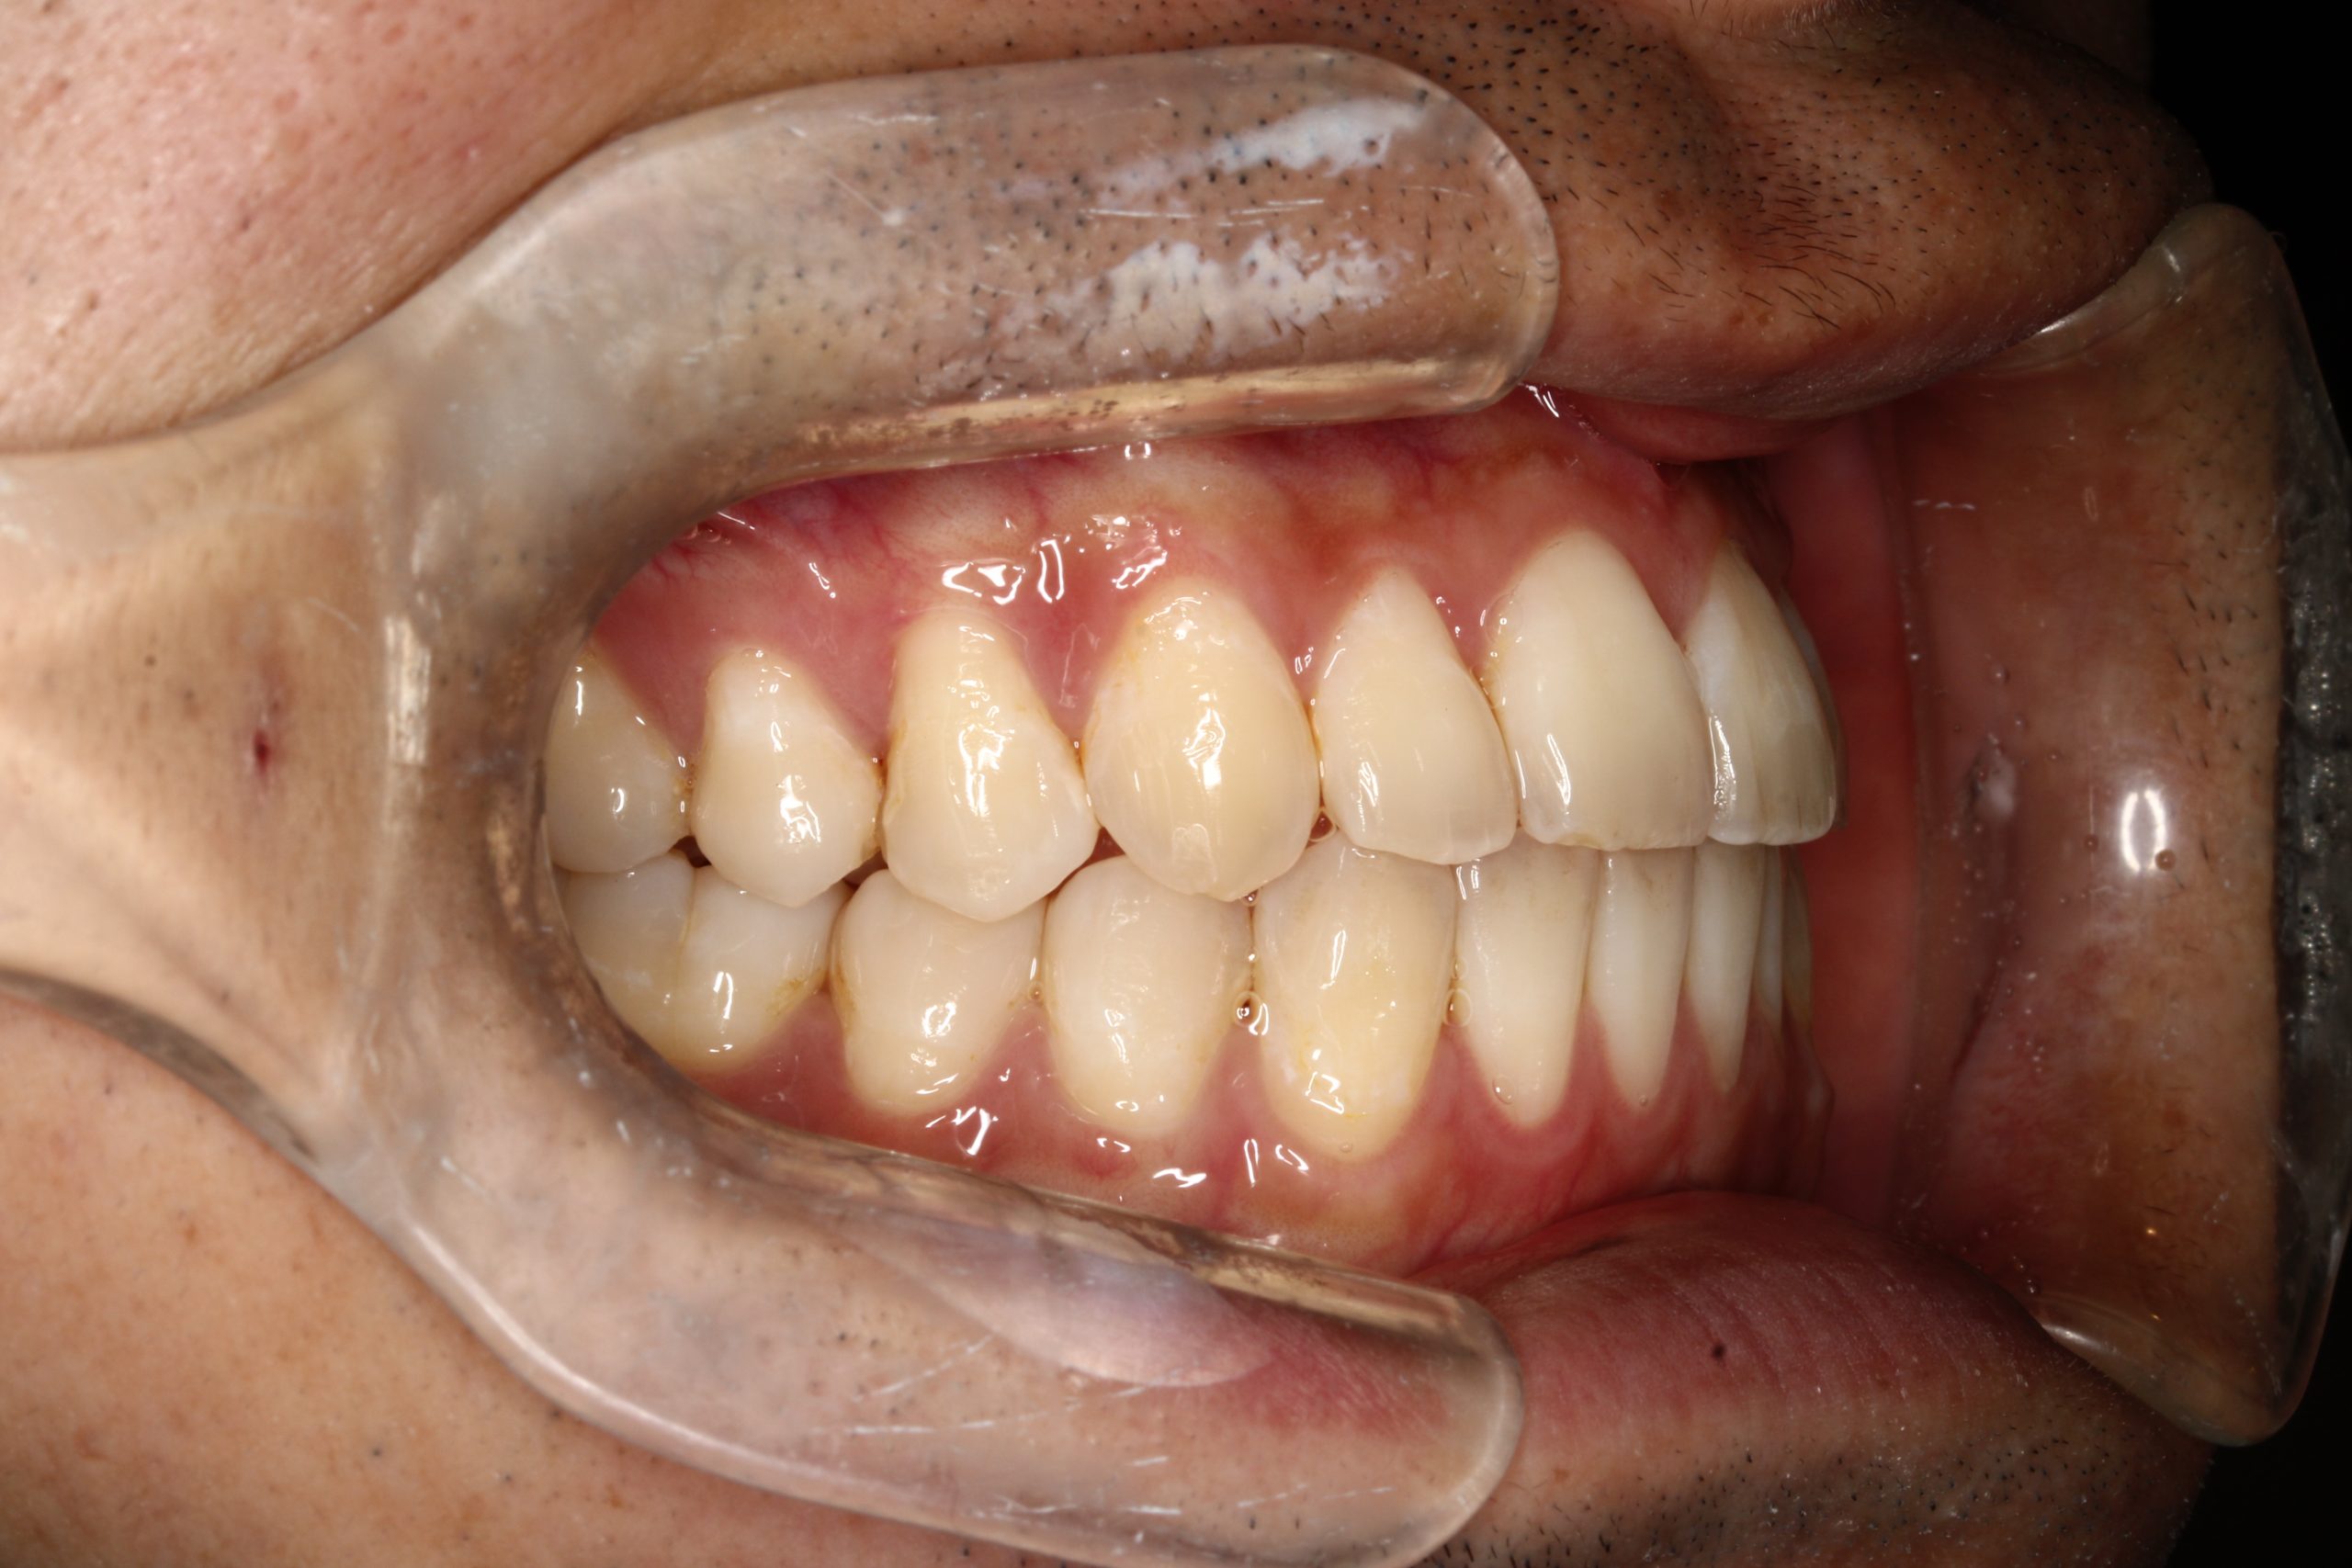

下の歯が出ている ・噛んだ時に、下の歯と上の歯がかみ合わない

| 主訴 | 下の歯が出ている ・かんだ時に、下の歯と上の歯がかみ合わない |

Before